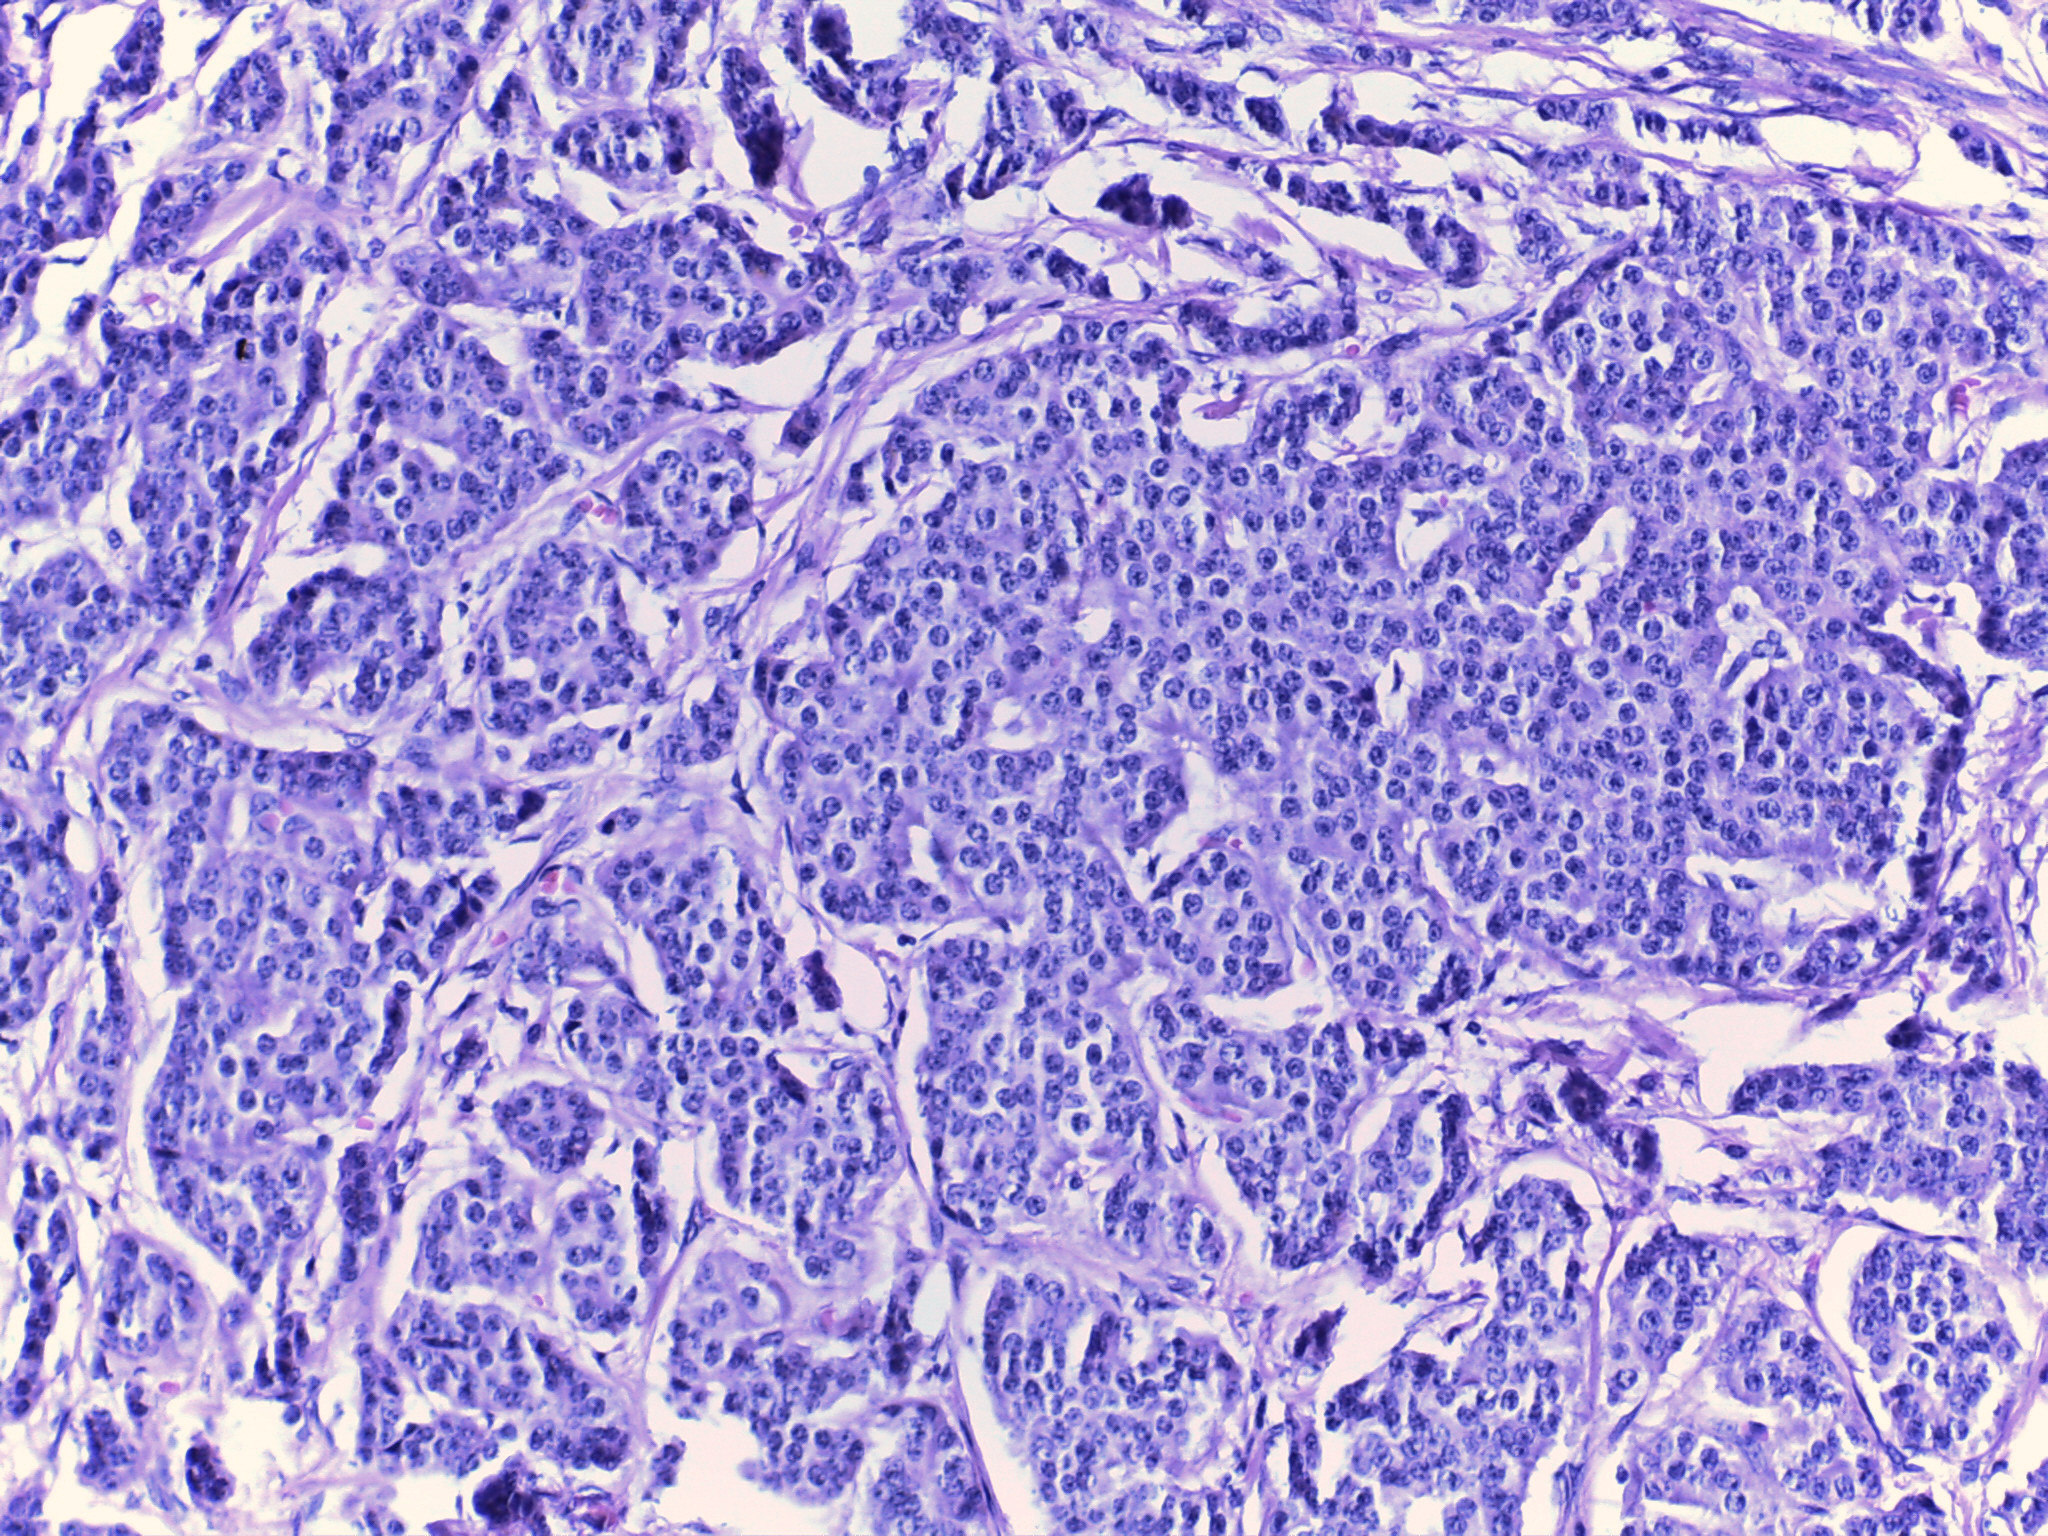

Hombre de 55 años con padecimiento de 1 año de evolución caracterizado por melena, astenia, adinamia y anemia. En enteroscopía se observaron múltiples lesiones subepiteliales en intestino delgado de una de las cuales se tomó biopsia.

Se realizó cirugía en la que se identificaron múltiples nódulos en ileon , entre los 80 y 120 cm de la válvula ileocecal. Se procedió a resección segmentaria de intestino.

Biopsia:

Cromogranina:

Ki 67:

Tumor neuroendocrino bien diferenciado grado 1